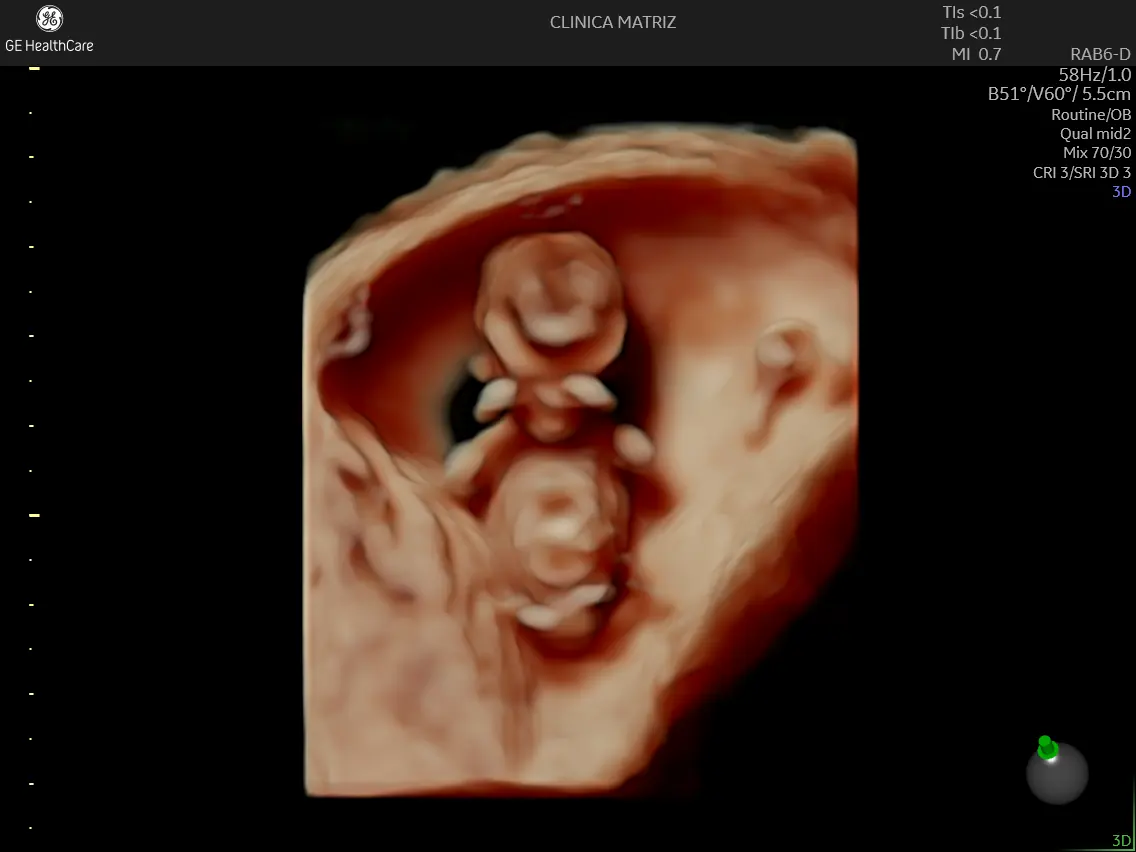

Ecografia 3D/4D: quando pode fazer sentido

A ecografia 3D/4D pode permitir visualizar contornos e superfícies com outro detalhe. Em termos clínicos, pode ser usada como complemento em situações selecionadas, mas a sua utilidade depende do objetivo, da posição fetal e de outros fatores (como a quantidade de líquido amniótico).